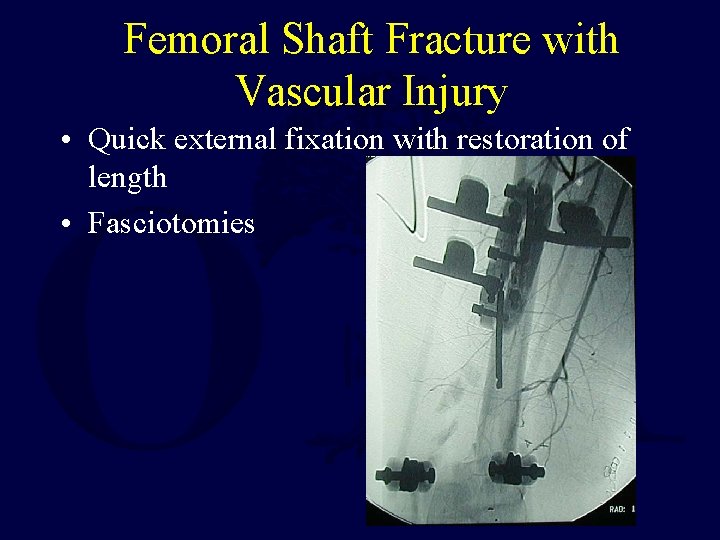

Femoral Shaft Fracture with Vascular Injury • Quick external fixation with restoration of length • Fasciotomies

Femoral Shaft Fracture with Vascular Injury • Exchange femoral nail either in same setting or in a few days • When found early plating or rodding of femur is rarely possible first • Do NOT perform IM nailing after arterial repair without initial length restoration